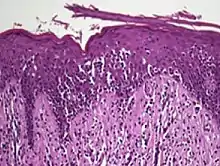

Histopathology of Pautrier microabscesses in cutaneous T cell lymphoma.

Pautrier's microabcesses are aggregates of four or more atypical lymphocytes arranged in the epidermis.[12] Pautrier microabcesses are characteristic of mycosis fungoides but are generally absent.

• the superficial papillary dermis is infiltrated by a bandlike lymphocyte infiltrate

• epidermotropism

• presence of atypical T-cells with cerebriform nuclei in the dermal and epidermal infiltrates.